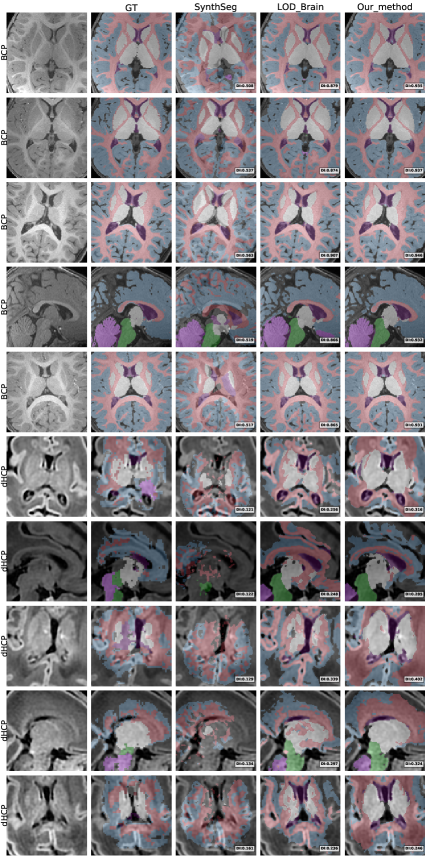

5.3 Evaluation on skull-stripped infant data

Due to the absence of ground-truth labels for the iSeg-19 validation set, we assess the performance of LODi through a qualitative comparison against the iBEAT V2.0 Cloud [Wang et al., 2023] model. iBEAT is a widely used infant brain segmentation framework which performs brain tissue segmentation into four primary classes: Gray Matter (GM), White Matter (WM), Cerebrospinal Fluid (CSF), and background. Fig. 8 presents a side-by-side visual comparison of segmentation outputs from our model and iBEAT, focusing on the four-label segmentation task, and highlighting differences in the delineation of key brain structures. This qualitative analysis provides insights into the model’s ability to generalize to unseen iSeg-19 data and maintain anatomical consistency across different segmentation approaches. By visually inspecting the segmentations, we observe that our model produces more accurate results than iBEAT, demonstrating effective adaptation to skull-stripped infant MRI scans and the model’s potential for reliable infant brain segmentation.